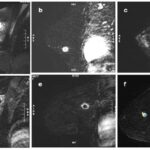

Anexo 3. Imágenes CMTN en resonancia magnética

Características en RNM del CMTN

En los resultados de las características en resonancia magnética, se debe tener en cuenta que de las 17 pacientes solo se dispone información de 8 resonancias magnéticas realizadas en centros periféricos. Esto representa el 75% de la muestra, equivalente a 8 casos.

De estos casos se destaca que informan una cantidad de tejido fibroglandular tipo B, aunque no describen el realce parenquimatoso de fondo ni hallazgos asociados.

En lo que respecta a la descripción nodular, se encontró que en el 77,7% de los casos (7 de 8) el nódulo se reportó como redondeado, seguido de la forma ovalada.

Los márgenes del nódulo en 7 casos se describen como circunscritos y solo en 1 caso se reporta como espiculado.

Según lo referido realce interno del nódulo, 5 casos presentaron realce heterogéneo periférico y 3 casos mostraron un realce en forma de anillo.

Finalmente, en la evaluación de la valoración de las curvas cinéticas, se notó que en la fase inicial los 8 casos tenían una fase rápida. En la fase tardía, 6 de los casos presentaban un patrón de wash out, mientras que 2 casos mostraban un tipo de realce en meseta.